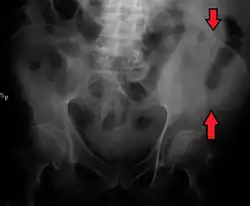

La cresta ilíaca es el nombre que recibe el borde superior del ala del ilion que se extiende hasta el margen de la pelvis mayor. La cresta ilíaca es palpable tanto en un hombre como en una mujer en toda su extensión,[1] de forma general convexa y levemente curva o sinuosa con concavidad interna en el frente y hacia afuera por detrás. Deja en su interior una cavidad que a menudo se denomina fosa iliaca.

La cresta ilíaca es más angosta hacia el centro que en los extremos y termina en la espina ilíaca antero-superior y posterior. La superficie de la cresta ilíaca es amplia y se puede dividir en un labio lateral o externo y un labio medial o interno y entre estos, una línea intermedia.[1]

La cresta ilíaca tiene una importante cantidad de médula ósea, incluso en el adulto, de modo que es un punto frecuente de extracción en la recolección de muestras de células madres para los trasplantes de médula ósea. El tope de la cresta ilíaca es el lugar donde se corresponde el cuerpo de la cuarta vértebra lumbar (L4), justo por encima o por debajo del cual se realiza la punción lumbar. La cresta iliaca es la mayor fuente de injerto óseo utilizada en cirugía maxilofacial, tanto de hueso esponjoso como de hueso corticoesponjoso.[3]